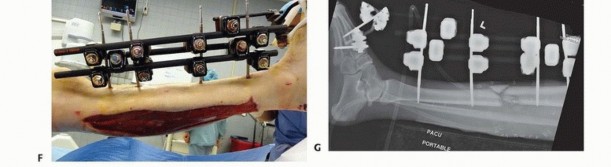

Ankle-Spanning Fixator for Tibial Pilon Fracture Two Schanz pins are placed into the midshaft tibial region ( TECH FIG 6). Avoid any compromised soft tissues and possible fracture extension if spanning the ankle for a severe pilon fracture with shaft extension.

### TECH FIG 6 • Ankle-spanning fixators bridging a severe pilon fracture. A,B. Two pins are placed into the proximal tibia, out of the distal fracture zone of injury. A calcaneal transfixion pin is placed through the calcaneal tuberosity and subsequent medial-lateral triangulation connecting bars are attached. Longitudinal traction is applied, and all bars are tightened to maintain reduction. A forefoot pin is placed into the first metatarsal to maintain the foot in a neutral position and avoid equinus contracture.

(continued)

A centrally threaded transfixion pin is then placed through the calcaneal tuberosity from medial to lateral, avoiding the posterior tibial artery. The appropriate location for this pin is 1.5 cm anterior to the posterior aspect of the heel and 1.5 cm proximal to the plantar aspect of the heel. This location is confirmed via fluoroscopy. A solitary bar is connected to the tibial pins. 543

### TECH FIG 6 •

C. Similar pin configuration with a triangular frame. First and fifth metatarsal pins with a forefoot bar were applied to maintain a neutral foot position. D. Skin demonstrates wrinkles and at this time is amenable to formal open reconstructive procedures. Medial and lateral bars are then connected to each side of the heel pin, making a triangular configuration. Longitudinal traction is carried out to obtain length, and care is taken to achieve appropriate anteroposterior reduction. To maintain a plantigrade foot and to maintain alignment, a pin is placed into the base of the first or second metatarsal. 15 This forefoot pin is then connected to the main frame with a connecting bar and the foot is held in neutral dorsiflexion. 1. ## Two-Pin Fixator: Temporary Stabilization for Tibial Shaft, Pilon, or Plateau Fractures This is a temporary frame designed for rapid distraction and gross reduction used for all types of tibial pathology. A proximal centrally threaded transfixion pin is applied one fingerbreadth proximal to the tip of the proximal fibula. It is inserted from lateral to medial ( TECH FIG 7A,B). Alternatively, this pin can be placed into the distal femur at the level of the midpatella along the midlateral condyle of the femur. A second transfixion pin is placed through the calcaneal tuberosity, similar to the ankle-spanning frame described earlier. Two long connecting bars are then attached to the pins on each side of the leg. Longitudinal traction is applied and a gross reduction is achieved. In some circumstances, a third pin is placed into the tibial shaft and attached to one of the longitudinal bars by a third connecting bar ( TECH FIG 7C,D). This is done to add stability to this very simple frame (TECH FIG 7E-G).